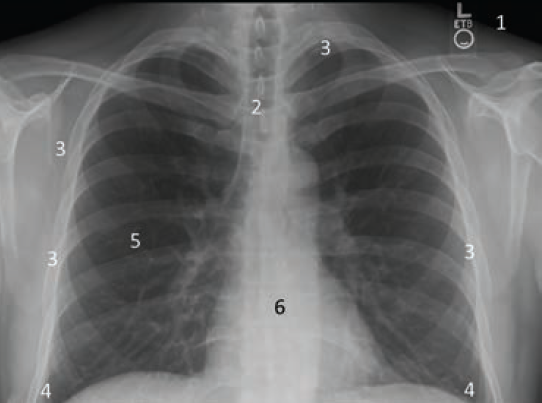

(Right panel) Cardiac silhouette as seen on a CXR, starting at the bottom of the cardiac silhouette at right diaphragm, the right atrial (RA) edge [1] moves upward, with the edge now representing the right pulmonary hilum [2], the overlap of the superior vena cava and ascending aorta [3], and upward to the top of ascending aorta moving to the transverse portion of the aorta [4] and then downward forming the aortic ‘knob’ [5] or bend at the transition of the transverse and descending aorta. The next portion of the silhouette is the left pulmonary hilum [6], the left atrial appendage segment [7], the left ventricle [8] and then the intersection with the left diaphragm.

Looking at a chest x-ray, recall how the heart is positioned in the chest (Figure 2). The fist-sized heart has a conical shape, with the base of the heart near the center line of the chest and the apex oriented at about 45 degrees toward the left of the center. On the CXR, the cardiac structures are outlined with edges made of overlapping structures. The most anterior structure is the right ventricle, but the left ventricle makes up much of the cardiac silhouette (Figure 3). Starting at the bottom of the cardiac silhouette at the right diaphragm, the right atrial (RA) edge (1) continues upward, with the edge now representing the right pulmonary hilum (2) further up, the overlap of the superior vena cava and ascending aorta (3) and upward to the top of ascending aorta, moving to the transverse portion of the aorta (4), and then downward, forming the aortic ‘knob’ (5) or bend at the transition of the transverse and descending aorta. The next portion of the silhouette is the left pulmonary hilum (6), the left atrial appendage segment (7), the left ventricle (8), and then the intersection with the left diaphragm.

On the left panel of Figure 3, an anterior view of the dissected heart can be appreciated in exquisite detail.